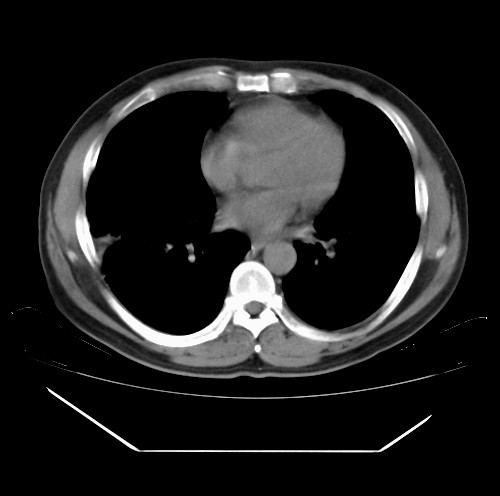

标题: CT22085:双肺多发结节

男,44岁,咳嗽,痰中带血2天。

除肺内及胸膜下可见多发大结节外,在肺小叶中心核、小叶间隔及支气管血管束上亦可见多方小结节,可以认为是随机分布。考虑转移可能性大。

仔细观察病灶形态,病灶边界部分清楚,结合临床症状,首先考虑转移,纵隔内多个肿大淋巴结影。

双肺血管纹理末端多发类圆形结节,边界光滑清晰 气管前腔静脉后淋巴结肿大

考虑转移瘤

本例双肺多发类圆形高密度灶,边清,结合病史多考虑双肺多发转移改变,可以结合实验室检查。